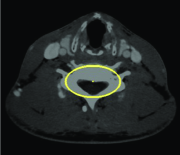

Similar interaction is utilized in 3D live-wire (Hamarneh et al., 2005) as implemented in the TurtleSeg software222www.turtleseg.org (Top and et al., 2011; Top et al., 2011). In 3D live-wire, few slices in different orientations of a 3D volume are segmented using 2D live-wire. Then, the segmented 2D slices are used to segment the whole 3D volume by generating additional contours on new slices automatically. The new contours are obtained by calculating optimal paths connecting the points of intersection between the new slice planes and the original contours provided semi-automatically by the user.